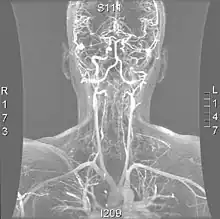

Magnetic resonance angiogram of the neck vessels in a person with Ehlers-Danlos syndrome type IV; it shows a dissection of the left internal carotid artery, dissection of both vertebral arteries in their V1 and V2 segments and a dissection of the middle and distal third of the right subclavian artery. Such striking episodes of dissection are typical for this "vascular" subtype of Ehlers-Danlos syndrome.

Various diagnostic modalities exist to demonstrate blood flow or absence thereof in the vertebral arteries. The gold standard is cerebral angiography (with or without digital subtraction angiography).[3][18][19] This involves puncture of a large artery (usually the femoral artery) and advancing an intravascular catheter through the aorta towards the vertebral arteries. At that point, radiocontrast is injected and its downstream flow captured on fluoroscopy (continuous X-ray imaging).[20] The vessel may appear stenotic (narrowed, 41–75%), occluded (blocked, 18–49%), or as an aneurysm (area of dilation, 5–13%). The narrowing may be described as "rat's tail" or "string sign".[1] Cerebral angiography is an invasive procedure, and it requires large volumes of radiocontrast that can cause complications such as kidney damage.[20] Angiography also does not directly demonstrate the blood in the vessel wall, as opposed to more modern modalities.[1][2] The only remaining use of angiography is when endovascular treatment is contemplated (see below).[1]

More modern methods involve computed tomography (CT angiography) and magnetic resonance imaging (MR angiography). They use smaller amounts of contrast and are not invasive. CT angiography and MR angiography are more or less equivalent when used to diagnose or exclude vertebral artery dissection.[18] CTA has the advantage of showing certain abnormalities earlier, tends to be available outside office hours, and can be performed rapidly.[1] When MR angiography is used, the best results are achieved in the T1 setting[2] using a protocol known as "fat suppression".[1][2][3] Doppler ultrasound is less useful as it provides little information about the part of the artery close to the skull base and in the vertebral foramina, and any abnormality detected on ultrasound would still require confirmation with CT or MRI.[1][2][3]